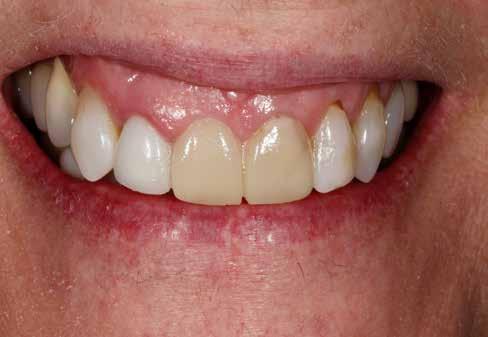

Elhagyott frontfogak, megtámadott parodoncium: a páciens kiindulási helyzete több mint nehéznek bizonyult. Yuki Momma és dr. William C. Heggerick, szerzőink, bemutatják, hogyan állítható helyre a harmónia a négy frontfog ellátásával.

A felső frontfogak állapota elhanyagolt, a parodontális struktúrák részben erősen károsodottak, VMK korona az 12 zónában, az ínyszél szürke, fekete approximális háromszögek… vörös-fehér esztétikáról nem is beszélhetünk (1. kép). Így jelentkezett a hölgypáciens a Weston Dental Specialists Group rendelőben. Elvárásai magasak voltak. A defektusok kezelését, a gingiva lefutásának korrigálását kívánta. Gyorsan világossá vált, hogy a megoldást csak a négy frontfog teljes kerámiakoronával való ellátása jelentheti. A jelen eset bemutatja, hogy az IPS e.max ZirCAD Prime segítségével hogyan lehet tiszta, tetszetős és esztétikus mosolyt létrehozni.

1. kép: Kiindulási helyzet.